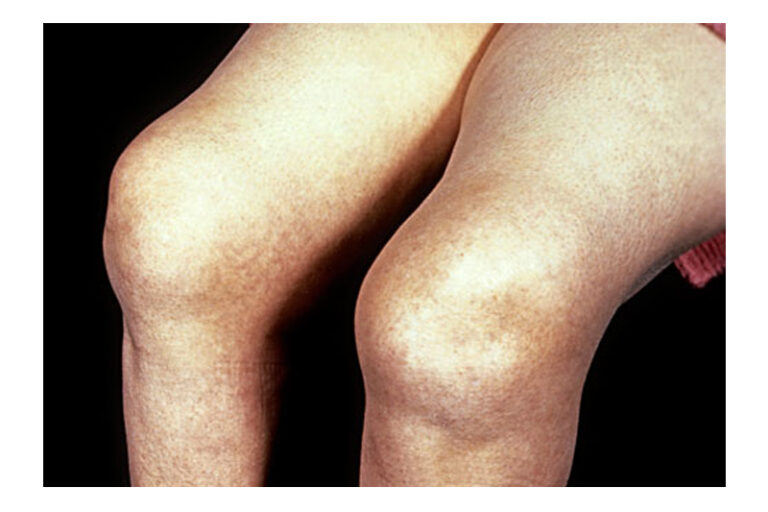

「鶴膝風」是個中醫病名,是指膝關節退化持續惡化,到了後期出現膝關節周圍腫脹、變形,周邊的肌肉萎縮,在外觀上看到膝蓋腫大變形,而上下的大腿、小腿變得瘦小,狀如鶴膝,故名「鶴膝風」。到了這個階段,患者通常都有膝關節屈伸困難,每當上下樓梯、上落斜路、下蹲時都會感到疼痛,當早上起床或休息後膝關節會僵硬,每當天氣變化時常誘發膝痛,嚴重影響病者的起居作息,部份甚至因膝關節畸形影響步態而要使用手杖輔助支撐身體。